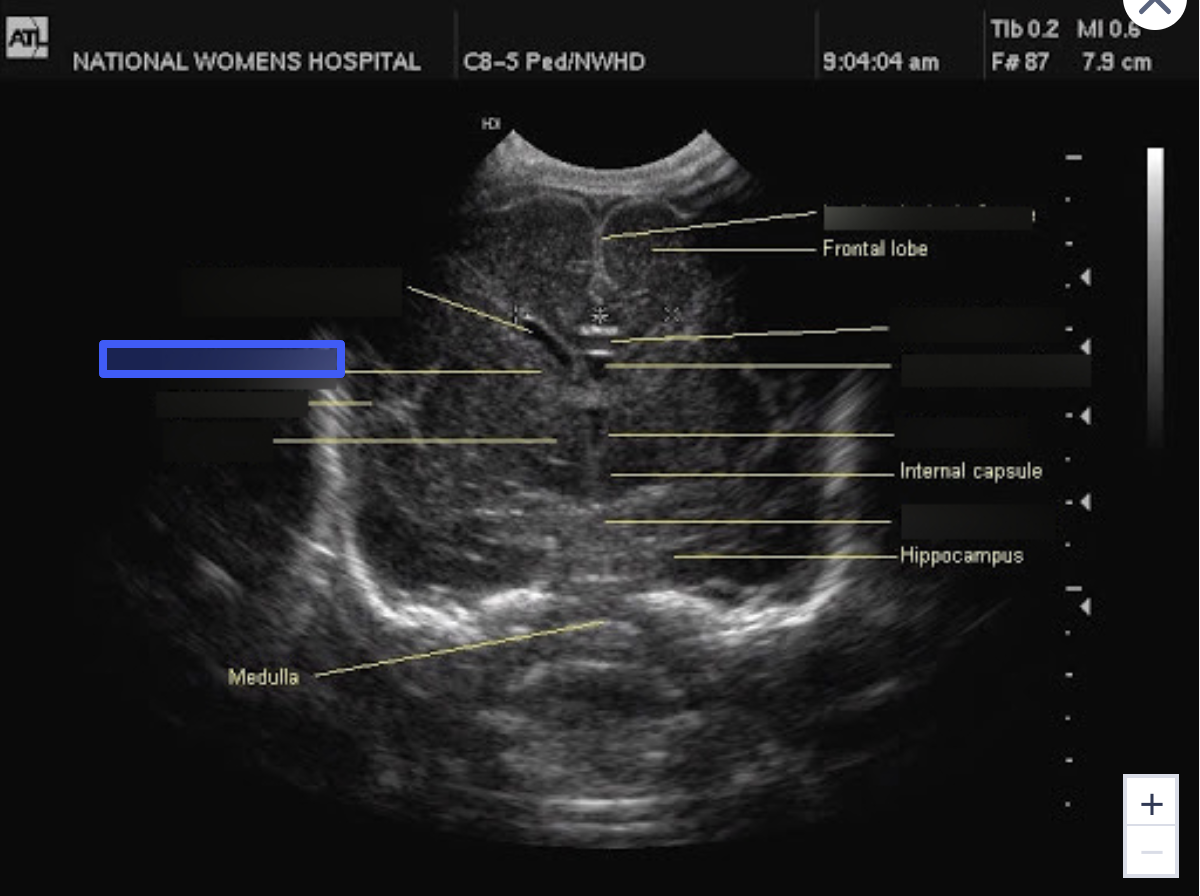

Frontal Lobe

What is number 5?

Parietal Lobe

What is number 6?

Temporal Lobe

What is number 7?